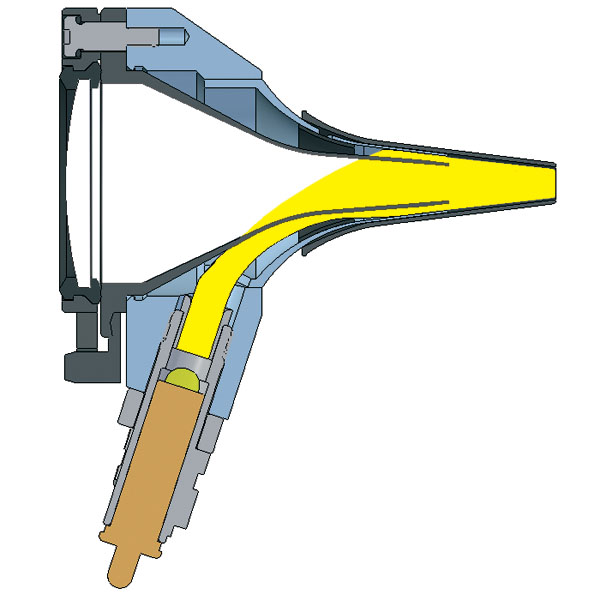

Ωτοσκόπιο Οπτικής Ίνας Heine K®180 Κεφαλή Ωτοσκοπίου ψυχρού φωτισμού από πολυκαρβονικά υλικά για γενική χρήση. Διαθέτει μεγάλο παράθυρο παρατήρησης & Θύρα πνευματοσκόπισης. Το παράθυρο περιστρέφεται και κλείνει αεροστεγώς. Περιφερειακός φωτισµός Οπτικής Ίνας µε τεχνολογία Αλογόνου (Xenon) XHL. Ομοιογενής, χωρίς αντανακλάσεις φωτισµός καναλιού ακοής και τυµπάνου. Μεγάλο παράθυρο παρατήρησης , μεγέθυνσης 3x. Ανεμπόδιστη εικόνα, χωρίς παραμορφώσεις. Αεροστεγές παράθυρο. Αξιόπιστη εξέταση πνευματοσκόπισης. Το παράθυρο περιστρέφεται και είναι βιδωμένο στην κεφαλή. Εύκολη χρήση και άλλων εργαλείων, δεν χάνεται. Από ανθεκτικά πολυκαρβονικά υλικά και ακρυλικό παράθυρο παρατήρησης που δεν χαράζεται. Το προιόν δεν συνοδεύεται από πηγή τροφοδοσίας (λαβή μπαταριών ή επίτοιχη τροφοδοσία).Για πλήρη λειτουργικότητα και απόδοση φωτισμού συνδυάστε το Ωτοσκόπιο Heine K®180 με λαβή επαναφορτιζόμενων μπαταριών ή επίτοιχη μονάδα τροφοδοσίας.